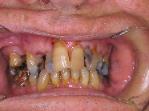

New patients will often come to our office feeling very embarassed, saying things like,

"You've never seen anything this bad before".  Well, we have.  This patient's mouth

was restored with a combination of crowns, bonding, partial denture and bleaching.

Eating is much easier, and he has a very nice smile.